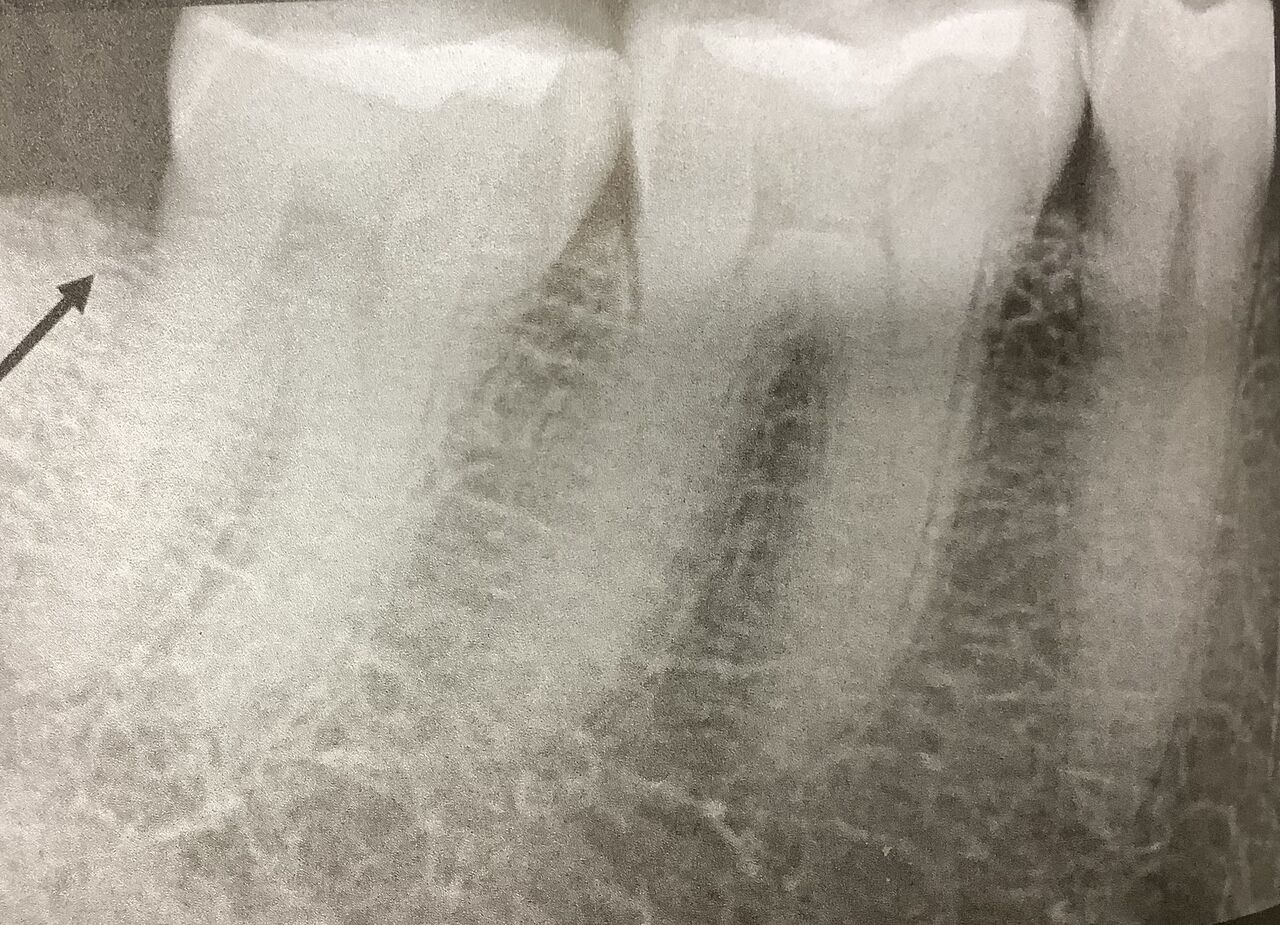

で、骨の溶け方から想像します。

ヒビに沿って、骨が痩せて見えます。

こんな感じに。

しかしこんな像は親知らずを抜いた跡だったり、歯周病でも起こります。

また二次元の画像では他のものが重なって、

見えなくなったりもします。